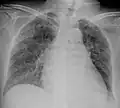

A case of miliary tuberculosis in an 82-year-old woman:

-

X-ray, 13 days after onset, showing bilateral interstitial infiltrates -

CT, 16 days after onset, showing extensive pulmonary parenchymal involvement consisting of irregular septal thickenings with ground-glass areas and centrilobular nodules with a peri-lymphatic distribution -

X-ray, 22 days after onset, showing extensive bilateral reticulo-nodular infiltrates -